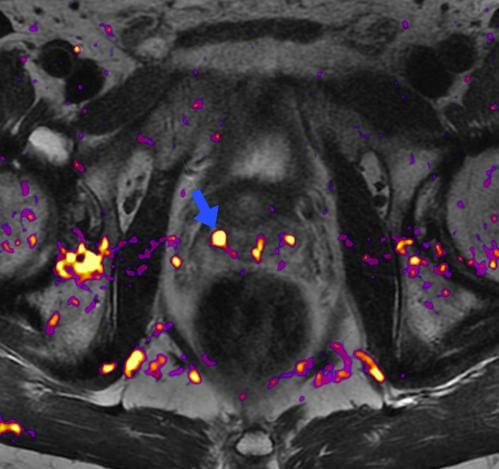

A male patient in his 60s was able to detect a 6 mm suspicious lesion in the right transitional zone in the mid-prostate gland. He was referred to an oncologist for additional evaluation.

Another example of how sensitive and effective enhanced imagery can be is illustrated in a 70-year-old male patient. From his MRI screening, we could see a 3.5 mm suspicious lesion in his right peripheral zone. We also referred him to an oncologist to establish evaluation and treatment.